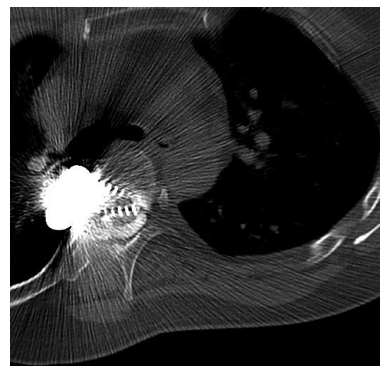

图2:20年前前路脊柱侧凸手术中放置的椎管内/髓内螺钉的胸椎椎管造影。